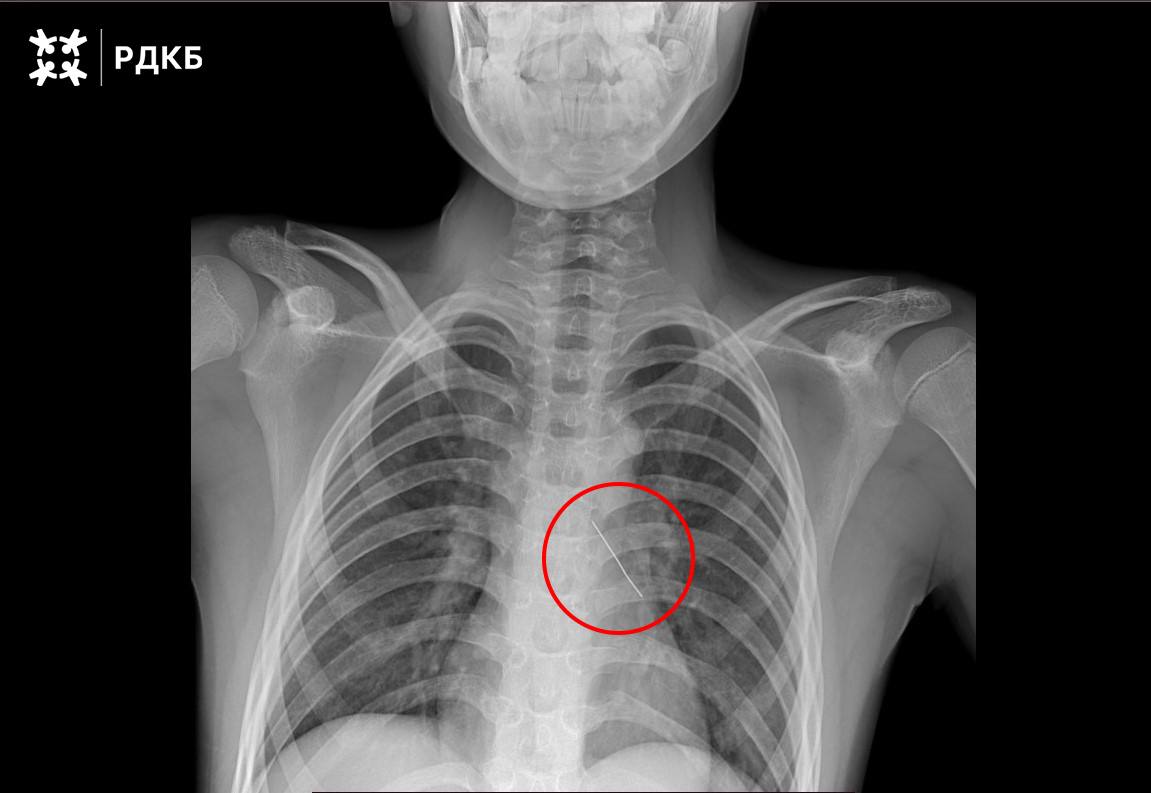

11-летний мальчик из Калининграда был экстренно доставлен в Москву, где врачи успешно извлекли булавку из его дыхательных путей.

11-летний мальчик из Калининграда был экстренно доставлен в Москву, где врачи успешно извлекли булавку из его дыхательных путей.

Московские хирурги совершили настоящее чудо, спася 11-летнего мальчика, который случайно вдохнул булавку. Подростка экстренно доставили бортом санавиации из Калининградской области в Российскую детскую клиническую больницу. 🚨

Операция прошла успешно: врачи аккуратно извлекли инородный предмет с помощью оптических щипцов. Уже через три дня мальчика выписали домой, и теперь он чувствует себя отлично. 💪